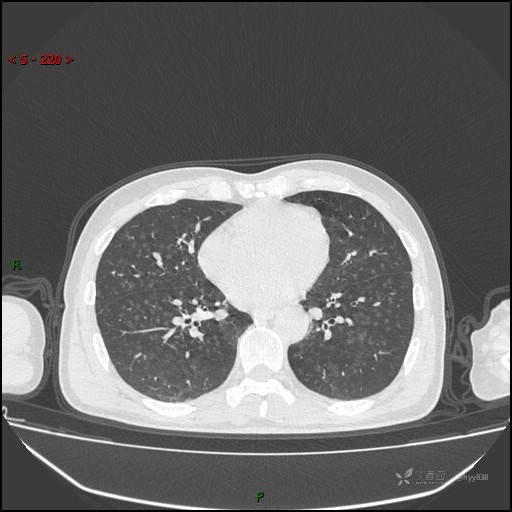

呼吸科电话会诊病例:过敏性肺炎 VS 吸烟相关间质性肺炎 VS 尘肺……结果公布~

性别:男

年龄:55岁

简要病史:渐进性呼吸困难。

胸部CT平扫

电焊工尘肺 (2)